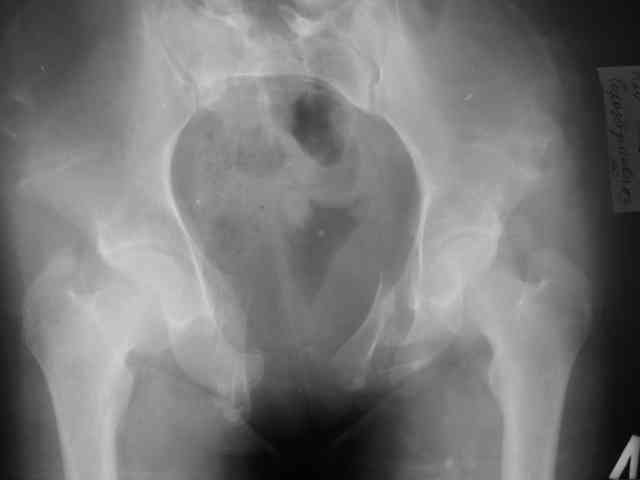

Уважаемый Алексей Владимирович и коллеги! Предоставляю Вашему вниманию неотдаленный результат лечения (5 месяцев) 20 летней девушки с переломом костей таза. Начало - http://weborto.net/forum/1143448738/index_html Укорочение левой нижней конечности 2 см. Снимки в 2 проекциях прилагаются. По ссылке на rapidshare можно скачать видео c функциональным результатом, ~11мб, ссылка будет работать 30 дней. Комментарии приветствуются. -- Best regards, Коваленко

Боли в покое отсутствуют, возникают при длительной ходьбе более 1.5км и длительном сидении. Половой жизнью пока не живет(до травмы тоже не жила). Как стоит-ходит - в видеоматериале.